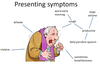

Symptoms of bronchiectasis

Characteristics of the cough in bronchiectasis

- productive

- worse in the morning

- large volume

- daily purulent sputum

3 major symptoms of bronchiectasis

- Persistent cough and purulent sputum

- Haemoptysis

- Fever, weight loss and malaise